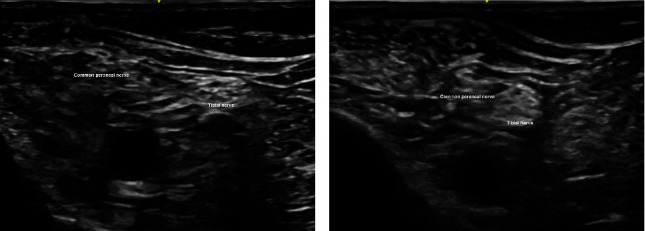

腓骨远端骨折是下肢常见的损伤。明显移位的腓骨远端骨折可在全身麻醉、脊髓麻醉或区域麻醉下进行手术固定治疗。我们介绍了一例腓骨远端移位骨折病例,区域麻醉和手术均由同一位骨科医生主治。患者成功接受了超声引导下的区域麻醉以及切开复位和内固定术。本病例报告重点介绍了超声引导下区域麻醉和外科医生手术固定的技术细节。

Distal fibula fracture is a common injury of the lower limb. Significantly displaced distal fibula fracture is treated with surgical fixation under general, spinal, or regional anesthesia. We present a case of displaced distal fibula fracture with both the regional anesthesia and operation performed by the same attending orthopedic surgeon. The patient underwent successful ultrasound-guided regional anesthesia as well as open reduction and internal fixation. This case report highlights the technical detail for ultrasound-guided regional anesthesia and surgical fixation by surgeon.